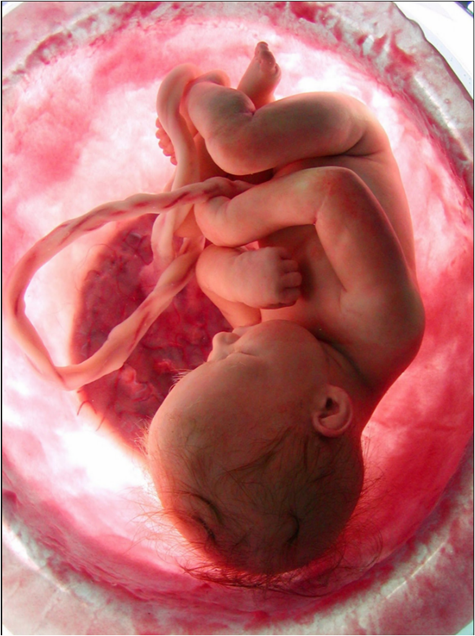

The word choroid means “like a chorion, membranous”, chorion refers to membrane enclosing the fetus, afterbirth; this is the outer membrane of the fetus. The word choroid dates to 1680 (Figure 1).

Figure 1. A six-week-old embryo seen together with the chorion. The chorion, here opened, surrounds the embryo. The external surface of the chorion is characterized by many tiny projections, the chorionic villi, which establishes an intimate connection with the lining of the uterus (endometrium). The part of the chorion at left will give rise to the placenta (With permission of the authors [18]).

Chorion is a membrane that develops around the developing fertilized egg. It begins to develop during the early stages of pregnancy, particularly after the young embryo implants in the uterine lining (endometrium) and form the germ layers. The chorion’s main job is to protect and nourish the developing baby inside the mother’s womb. It also helps to create a barrier between the mother’s blood and the baby’s blood to prevent any harmful substances from passing through, like the blood brain barrier in the CNS. The fetal placenta is also referred to as the chorion frondosum.

The chorion is a thin, transparent membrane that surrounds the developing embryo. It is made up of several layers of cells, each with its own unique function (Figure 2 and 3).